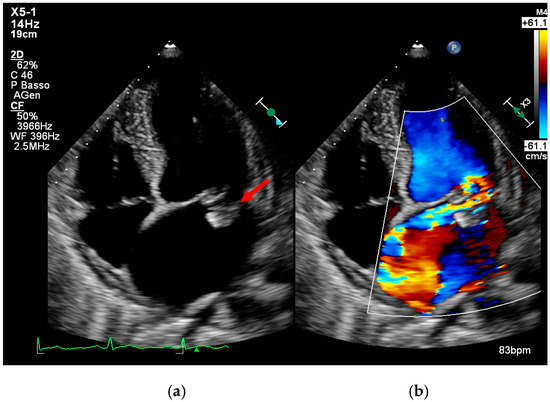

Multimodality Imaging in Infective Endocarditis: A Clinical Approach to Diagnosis

by Leonardo Brugiatelli, Francesca Patani, Carla Lofiego, Martina Benedetti, Irene Capodaglio, Pongetti Giulia, Francioni Matteo, Paolini Enrico, Nazziconi Marco, Kevin Maurizi, Furlani Giulia, Massari Arianna, Luciani Simone, Anselmi Benedetta, Gatti Chiara, Schicchi Nicolò, Fogante Marco, Tarsi Giovanni, Dello Russo Antonio, Di Eusanio Marco, Marini Marco and Fabio Vagnarelliadd Show full author list remove Hide full author list

Medicina 2025, 61(12), 2241; https://doi.org/10.3390/medicina61122241 - 18 Dec 2025

Infective endocarditis (IE) is a life-threatening condition with a rising incidence, demanding rapid and precise diagnosis. While echocardiography remains the cornerstone of initial evaluation, its limitations in complex cases—such as those involving prosthetic valves or cardiac devices—are well-known. This review synthesizes current evidence [...] Read more.

Infective endocarditis (IE) is a life-threatening condition with a rising incidence, demanding rapid and precise diagnosis. While echocardiography remains the cornerstone of initial evaluation, its limitations in complex cases—such as those involving prosthetic valves or cardiac devices—are well-known. This review synthesizes current evidence and guidelines to outline a practical, multimodality imaging approach for IE. We emphasize that integrating advanced techniques like cardiac computed tomography (CT) and [18F]-fluorodeoxyglucose positron emission tomography/computed tomography (FDG PET/CT) early in the diagnostic pathway, particularly in high-risk scenarios, significantly enhances diagnostic certainty, guides therapeutic decisions, and improves patient outcomes. A tailored imaging strategy, driven by clinical presentation and integrated within a multidisciplinary endocarditis team, is paramount for modern IE management. Full article

(This article belongs to the Special Issue Diagnosis and Treatment of Valvular Heart Diseases)

Show Figures

Figure 1